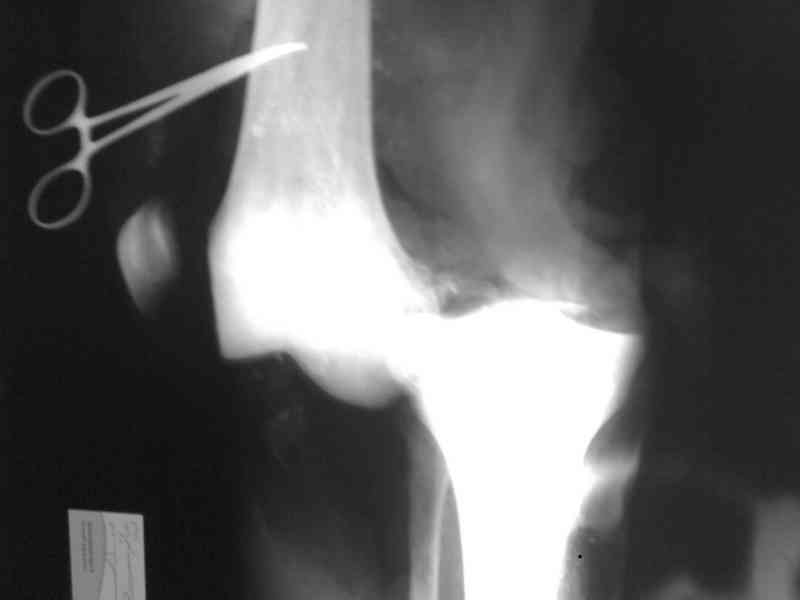

Uvajaemiy kollega! *Pomosh okazano v nujnom ob`eme*- kak ponyat? Vosstanovili krestoobraznih i bokovih svyazok? ili prosto vivih vpravili i fiksirovali AVF. sudya po R-snimkam nadkolennik nahoditsya visoko- znachit povrejdena i sobstvennaya svyazka, kotoraya ne ushita. Potom mojno sostavit plan lecheniya. S uvajeniem Abdurashid.

На ренгенограмме хорошая аппозиция костей коленного сустава, но надколенник находится подозрительно высоко, поэтому необходимо убедиться в отсутствии повреждения связки надколенника.

Наличие пульсации на конечностях еще не доказательство отсутствия интимальных повреждении сосудов, наблюдались вторичные осложнениия, поэтому важна консультация сосудистого специалиста.

Снимки прошлых публикации из моего Power point